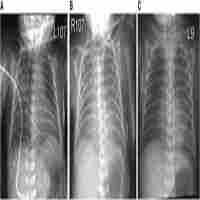

| Abstract | Background Central and peripheral nervous system symptoms and complications are being increasingly recognized among individuals with pandemic SARS-CoV-2 infections, but actual detection of the virus or its RNA in the central nervous system has rarely been sought or demonstrated. Severe or fatal illnesses are attributed to SARS-CoV-2, generally without attempting to evaluate for alternative causes or co-pathogens. Case presentation A five-year-old girl with fever and headache was diagnosed with acute SARS-CoV-2-associated meningoencephalitis based on the detection of its RNA on a nasopharyngeal swab, cerebrospinal fluid analysis, and magnetic resonance imaging findings. Serial serologic tests for SARS-CoV-2 IgG and IgA showed seroconversion, consistent with an acute infection. Mental status and brain imaging findings gradually worsened despite antiviral therapy and intravenous dexamethasone. Decompressive suboccipital craniectomy for brain herniation with cerebellar biopsy on day 30 of illness, shortly before death, revealed SARS-CoV-2 RNA in cerebellar tissue using the Centers for Disease Control and Prevention 2019-nCoV Real-Time Reverse Transcriptase-PCR Diagnostic Panel. On histopathology, necrotizing granulomas with numerous acid-fast bacilli were visualized, and Mycobacterium tuberculosis complex DNA was detected by PCR. Ventricular cerebrospinal fluid that day was negative for mycobacterial DNA. Tracheal aspirate samples for mycobacterial DNA and culture from days 22 and 27 of illness were negative by PCR but grew Mycobacterium tuberculosis after 8 weeks, long after the child’s passing. She had no known exposures to tuberculosis and no chest radiographic findings to suggest it. All 6 family members had normal chest radiographs and negative interferon-γ release assay results. The source of her tuberculous infection was not identified, and further investigations by the local health department were not possible because of the State of Michigan-mandated lockdown for control of SARS-CoV-2 spread. Conclusion The detection of SARS-CoV-2 RNA in cerebellar tissue and the demonstration of seroconversion in IgG and IgA assays was consistent with acute SARS-CoV-2 infection of the central nervous infection. However, the cause of death was brain herniation from her rapidly progressive central nervous system tuberculosis. SARS-CoV-2 may mask or worsen occult tuberculous infection with severe or fatal consequences. |